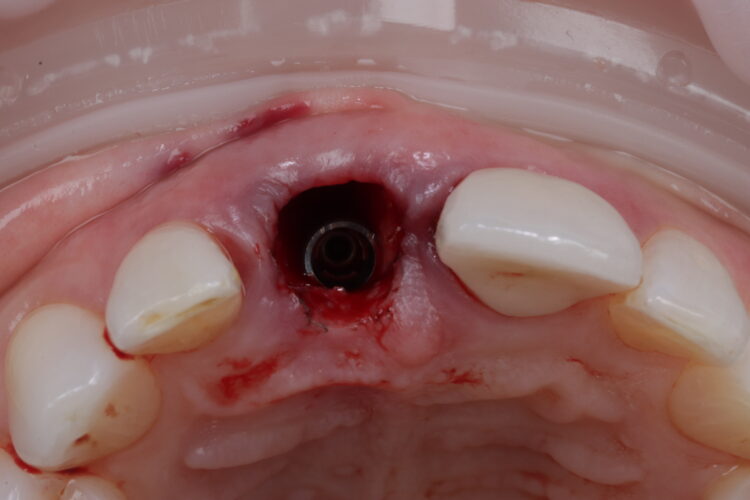

On the day of surgery, the post crown was removed, and the tooth sectioned to ease extraction while preserving the buccal plate. Forceps were used to deliver the fragments, with extensions to simplify pick-up (Hu-Friedy). The granulation tissue was removed using a Lucas curette.

The surgical guide was checked in the mouth, ensuring it was fully seating and not in contact with the adjacent teeth.

The standard CONELOG® (BioHorizons Camlog) guided drill sequence was followed. The Guided Surgical Kit is very simple to use with a streamlined number of drills. The CONELOG® drills support primary stability, with side-cutting features and apical threads that engage the native bone.

The CONELOG® Progressive-line implant maximised primary stability and in this case the implant was inserted at 70Ncm. The pre-made temporary was used as the temporary restoration; however, there would also be the option of modifying the existing crown.

The implant was placed in close contact with the palatal bone, 1mm below the buccal bone height. A temporary cylinder abutment was connected, with flowable composite placed to attach the temporary restoration. The composite resin was used to create the optimal emergence profile ensuring a highly polished restoration in the transition zone.